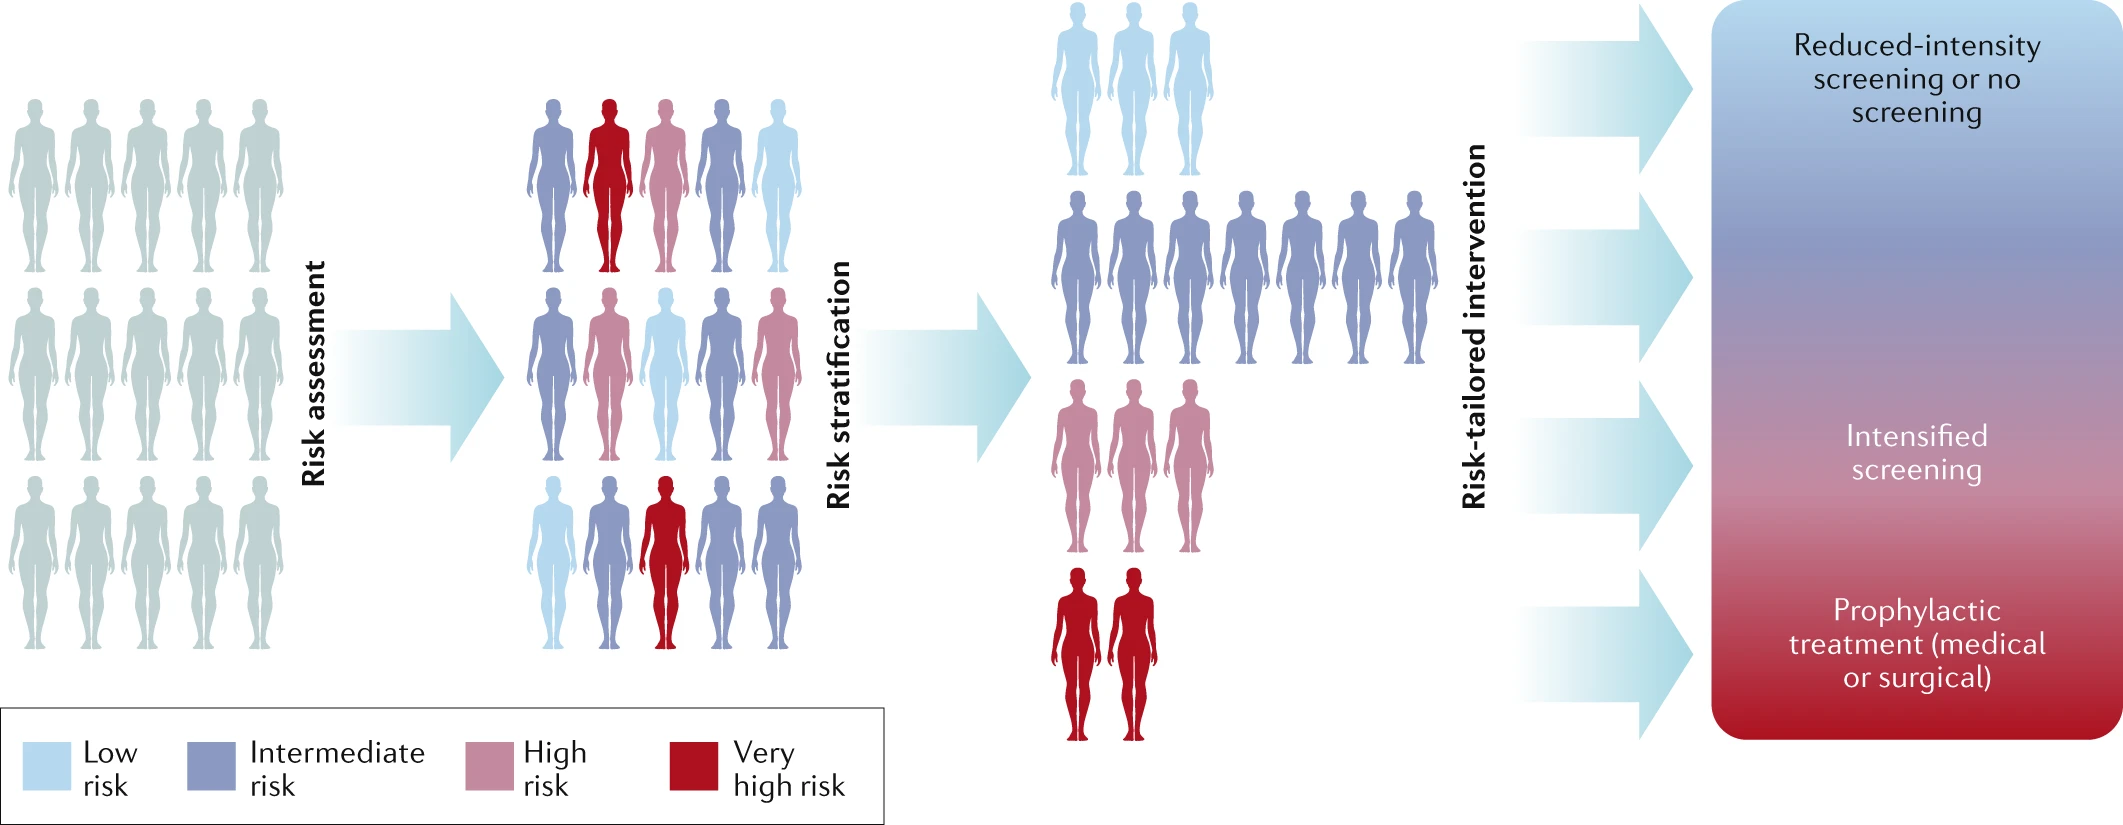

Polygenic risk scores for breast cancer prevention: a guide for physicians

A how-to guide for how to use breast cancer polygenic risk scores

Polygenic Risk Scores (PRS) are a powerful tool in precision medicine, offering insights into an individual’s genetic predisposition to various diseases.

Polygenic risk scores (PRS) predict the likelihood of developing complex diseases based on an individual’s genetic makeup. However, their application across different genetic ancestries presents numerous challenges.

It is time for polygenic risk scores to be used in breast cancer risk assessments

Much of the development of polygenic risk scores (PRSs) centers on assessing their ability to predict risk in different populations. This undoubtedly provides assurance of their clinical validity, which is a crucial component of PRS development...